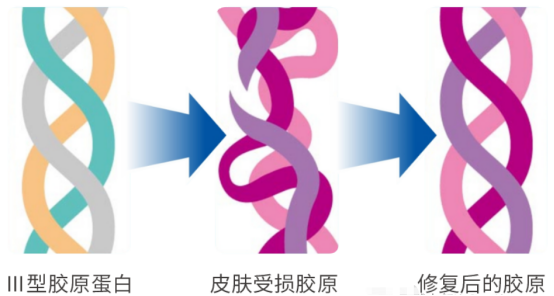

械二类医用精华,医用重组胶原蛋白修护液产品介绍

时间:2024-05-24湖南微肽生物医药有限公司——医用重组胶原蛋白修护液 什么是重组Ⅲ型人源胶原蛋白? 重组人源Ⅲ型胶原蛋白是采用基因工程DNA重组技术,通过MRNA逆转录成人源细胞的DNA而成的三螺旋结构活性胶原蛋白,其氨基酸组成与人体天然的胶原蛋白氨基酸序列100%相同,无免疫排…查看全文

医用重组三型人源胶原蛋白敷料的作用、功效,以及适用范围

时间:2024-05-14湖南微肽生物医药有限公司——医用重组三型人源胶原蛋白敷料 医用重组三型人源胶原蛋白敷料是一种新型的医学敷料,由人体进化历史上最原始和基础的重组Ⅲ型胶原蛋白制成。这种敷料具有优异的生物相容性和生物活性,可以用于各种类型的皮肤创伤,如烧伤、烫伤、划伤、挫伤、擦伤等,以及手术切口、…查看全文